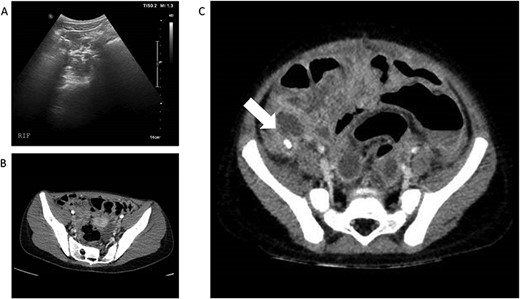

(A) and (B)—Case 1: abdominal ultrasound scan and computed tomography (CT) scan of abdomen, (C)—Case 2: CT scan of abdomen; white arrow shows faecolith with inflamed appendix and surrounding collections.

Patient B, a 3-year-old boy, presented similarly with a 4 day history of abdominal pain, non-bilious vomiting and high temperatures. He had normal observations for his age but had abdominal distension and a tender lower abdomen. He also had a raised CRP along with an elevated D-Dimer and raised Ferritin (Table 1). A-USS and echocardiogram performed on Day 1 of admission were normal and he was SARS-CoV-2 positive on nasopharyngeal swab. Intravenous piperacillin and tazobactam were commenced to treat for possible concurrent sepsis and a presumptive diagnosis of PIMS-TS was made. Over the subsequent 12 hours he deteriorated with worsening pain and vomiting but it was noted that his CRP had reduced from 261 mg/L to 171 mg/L. Abdominal CT scan was undertaken and revealed perforated appendicitis with intra-abdominal collections (Fig. 1C). He underwent open appendicectomy without immediate complication and recovered well. He was treated for a superficial wound infection 7 days post-operatively with oral antibiotics.

Examination findings revealed the patient to be mildly tachycardic but normotensive. She was apyrexial and had abdominal tenderness centrally and in the right iliac fossa and was reported to be Rosving’s positive. The patient had markedly raised C-reactive protein (CRP) and lymphopenia along with a high D-Dimer and elevated ferritin. Her transaminases were also noted to be mildly elevated (Table 1). Abdominal ultrasound scan (A-USS) demonstrated mesenteric adenitis without free fluid and chest X-ray was unremarkable. Within 12 hours of admission she developed a palmar rash, followed by shock. Urgent computed tomography (CT) scan of the chest and abdomen revealed diffuse intra- and interlobar thickening consistent with SARS-CoV-2 infection and no intra-abdominal pathology (Fig. 1A and B). She was SARS-CoV-2 negative on reverse transcriptase polymerase chain reaction. Patient A was treated successfully for PIMS-TS with supportive care including antibiotics until the blood cultures were negative and the interleukin-1 antagonist anakinra [3]. The patient underwent an echocardiogram on Day 8 and was found to have left coronary artery ectasia and has ongoing follow-up of this important sequelae of PIMS-TS.